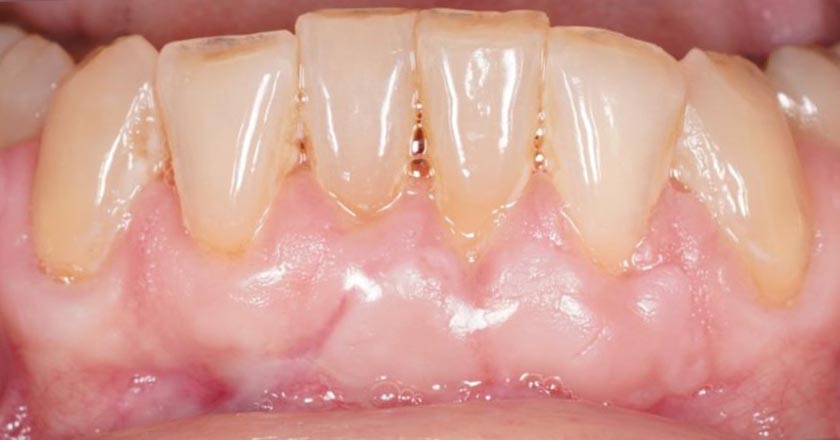

Gum Graft Lower - Before And After

Gum Graft Upper - Before And After